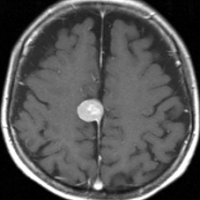

典型的な髄膜腫

この髄膜腫は中程度の大きさのものです。円蓋部髄膜種という最も多い最も手術の簡単なタイプです。麻痺や失語症やてんかんなどの症状はありません。とても美しくて若い女性の髄膜腫でしたが,子供に遺伝はしませんし,癌などと違ってタバコなどこれといった原因がなくて発生するものです。

MRIでの髄膜腫の見え方は撮影の仕方によっていろいろです。左からT1強調画像,T2強調画像,フレア画像といいます。腫瘍の横に小さく白い領域がありますが,これは脳の腫れた部分で脳浮腫といいます。髄膜腫があると周囲に脳浮腫が生じることがあります。

最も見やすいのが,ガドリニウム造影剤を注射して撮影するものです。一般的に髄膜腫は造影剤で白く映し出されます。この腫瘍は左脳側にあります。MRIの軸面という輪切りの写真では左右が逆になりますから注意してください。脳を下から見た図になっています。MRIはいろいろな方向から腫瘍を見ることができますが,右は冠状断という正面から見た図です。よく見ると腫瘍の上と下のはじっこに線状に糸を引いたように造影される部分があります。これをテールサイン(しっぽのサイン)といいます。腫瘍が硬膜に沿って延びている可能性があることを示しています。